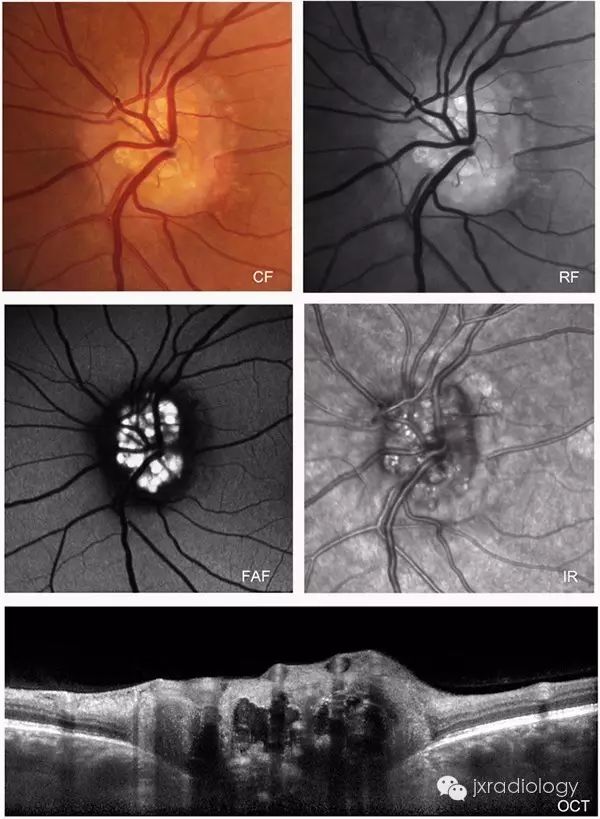

眼底镜检查结果取决于玻璃疣位于视盘中的深度。浅表沉积物表现出特征性自发荧光,在这种情况下的诊断是显而易见。更深的沉积物具有较少特异性的外观,其具有模拟乳头状水肿(伪乳头状水肿)的视盘肿胀。

1 影像学检查简介

眼底自发荧光(fundus autonflorescence,FAF)是一种无创呈现视网膜色素上皮(retinal pigmentalepithelium,RPE)及視网膜病理改变和疾病状态的成像方法。用光照激发荧光团,发出一个较长波长的光。FAF荧光的来源是内源性的,需要不同激发波长的光。目前,临床上应用较多的是用共焦扫描激光眼底镜下(confocal scanning laser ophthalmoscope,cSLO)记录的488 nm激光激发的大于500 nm的短波长自发荧光(short wavelength autofluorescence,SW-AF)和787 nm激光激发的大于800 nm的长波长的近红外自发荧光(near infrared autofluorescence,NIR-AF),前者的表现与脂褐质的分布有明显相关性。由于黄斑黄色素的遮挡和中心凹下RPE中脂褐质含量较少,黄斑中心凹AF明显减弱,最强的AF呈环形分布在黄斑边缘;后者反映的是眼底黑色素的分布,黄斑部由于RPE内黑色素较多,呈现出一个强的FAF区[1]。

眼底血管造影术包括以荧光素钠为染料,波长490 nm的蓝色可见光为激发光的荧光素眼底血管造影(fundus fluorescein angiography,FFA)及以吲哚青绿为染料,波长805 nm的近红外光为激发光的吲哚青绿血管造影(indocyanine green angiography,ICGA)。前者主要用于观察视网膜循环及视网膜屏障的异常改变,后者主要观察脉络膜血管病变。

相干光断层成像术(optical coherence tomography,OCT)利用近红外光对眼内组织结构进行断层扫描,起到类似组织病理学观察的作用,提供了一种无创、显微水平的视网膜活体观察手段。最新的OCT由于采用了傅立叶技术处理反射光信号,扫描速度可以大幅度地提高;眼球跟踪技术减少了误差干扰,使OCT像的轴向分辨率达到10 μm。

2.5视盘玻璃膜疣 视盘玻璃膜疣(optic disc drusen,ODD)是一种与视网膜玻璃膜疣名称相同而病理改变及发病机制迥异的疾病,其可分为原发性和继发性两种,后者继发于炎症和外伤。在此所述为与先天有关的原发性视盘玻璃膜疣。其发病机制有研究认为可能是基因突变引起;另有研究认为是因视神经纤维轴浆崩解、钙化或先天性的血管异常造成的血浆蛋白传输障碍郁积在视盘引起。电子显微镜下见玻璃膜疣多位于视盘筛板前区、视盘内有大小不一、呈环板状排列的无细胞结构的嗜碱性小体[2]。根据玻璃膜疣病变位置的深浅有可分为埋藏性玻璃膜疣和表面性玻璃膜疣。表面性玻璃膜疣眼底检查可见视盘结节状胶样隆起,并可融合为不规则的较大团块向玻璃体内突出如桑葚状,较易诊断。埋藏性ODD的眼底影像学表现显示视乳头轻度隆起,边界欠清晰,有时显示假性视乳头水肿。因疣体压迫、损伤视乳头上或周围毛细血管,可引起视盘或其周围视网膜出血。自发荧光表现为视盘自发荧光。FFA对诊断埋藏性玻璃膜疣具有极其重要的价值,造影早期视盘局部荧光素明显增强,造影后期玻璃膜疣处荧光素染色明显,但无荧光素渗漏。OCT检查可见患眼视盘视网膜神经纤维层(RNFL)高度隆起,其下方可见团块状高反射信号。B超是诊断ODD最有效的方法,因疣内存在钙质,检测结果会显示有强回声光团存在于视盘强方,其周边显示呈暗区,降低增益,光团不消失。有研究[18]发现对埋藏性视盘玻璃膜疣使用B超联合OCT检查,是非常可靠的诊断方法,两者联合应用,可有效提高检出率。有学者[19]认为,将玻璃膜与视网膜色素上皮层之间的drusen定义为玻璃膜疣,而将发生在视盘的drusen定义为视盘玻璃疣,这样可以更加明确drusen的概念。3 总结